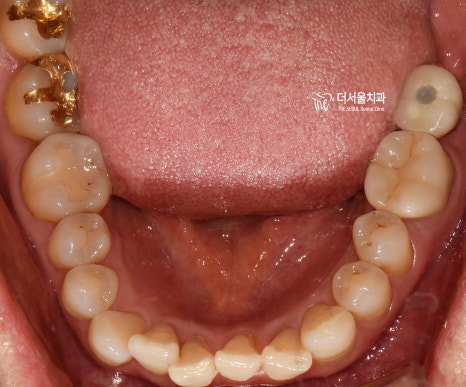

3개월 뒤,

맞춤형 지대주로 기둥을 끼워드리고

지르코니아를 연결해 드리면서

네비게이션 임플란트 수술이 끝나게 되었습니다.